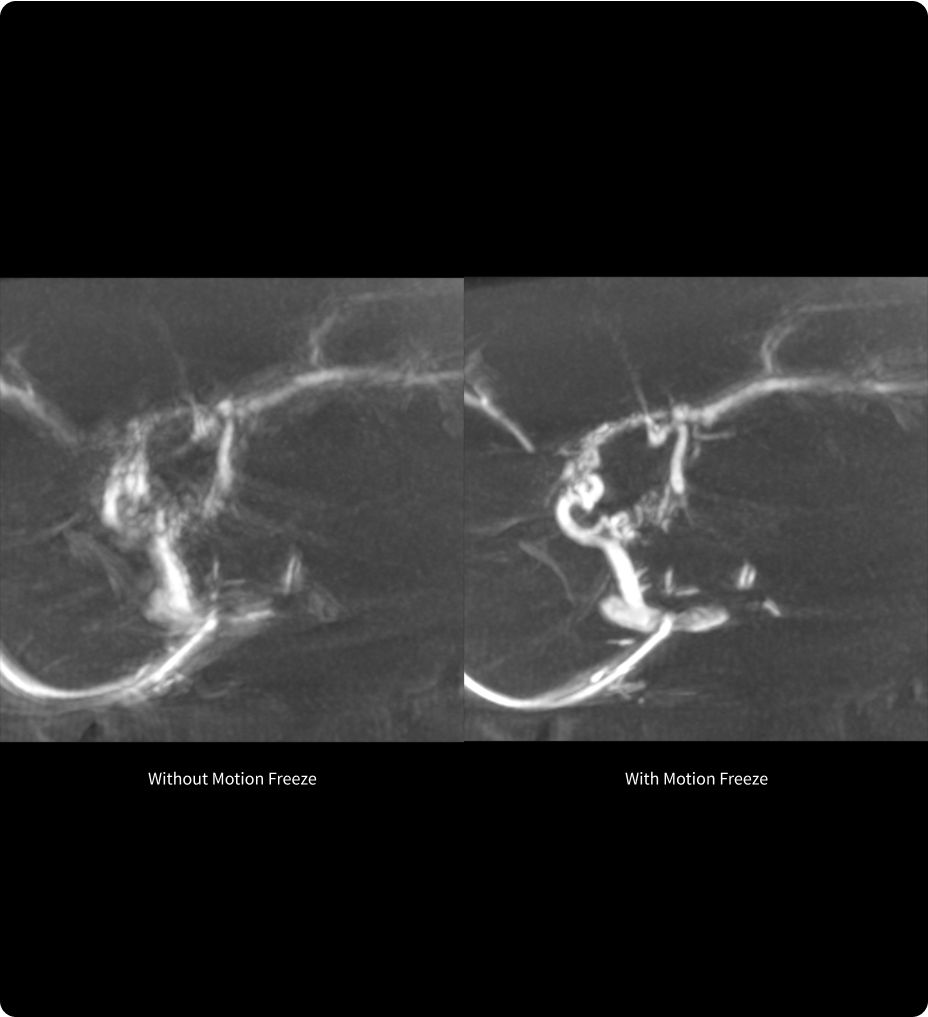

Available on all Revolution Ascend Platform configurations, Effortless Workflow intelligently automates your CT workflow from pre-scan protocoling to post-scan processing. It uses AI-based features to help transform the entire CT experience and provides maximum efficiency, accuracy, clarity and consistency.

This enables technologists to automatically and accurately personalize scans for each patient with significantly less effort. The end result is a beautiful CT image acquired in less time.